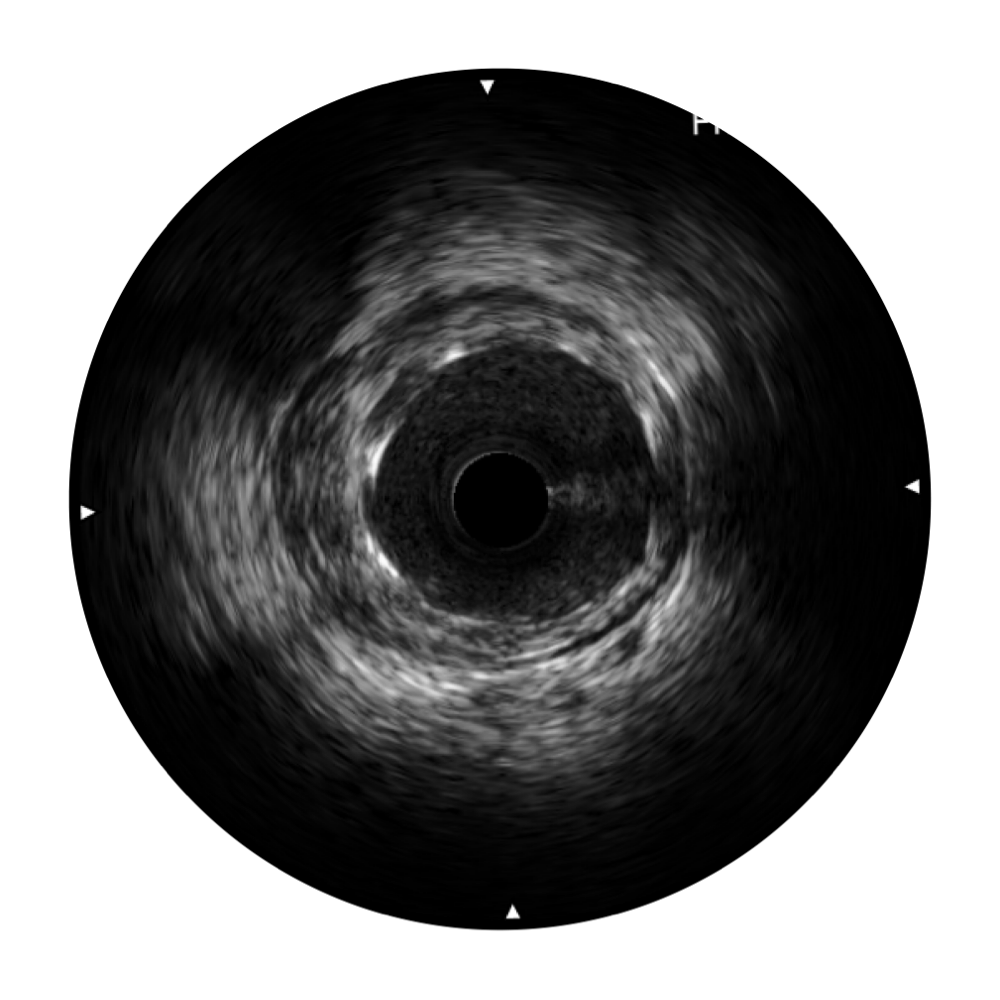

亚星官网宽频IVUS图像

传统IVUS图像

对比传统IVUS导管成像,亚星官网宽频IVUS图像的近场支架梁显影更细腻,远场中膜外血管仍清晰可辨,兼顾远中近,兼顾分辨力与穿透深度